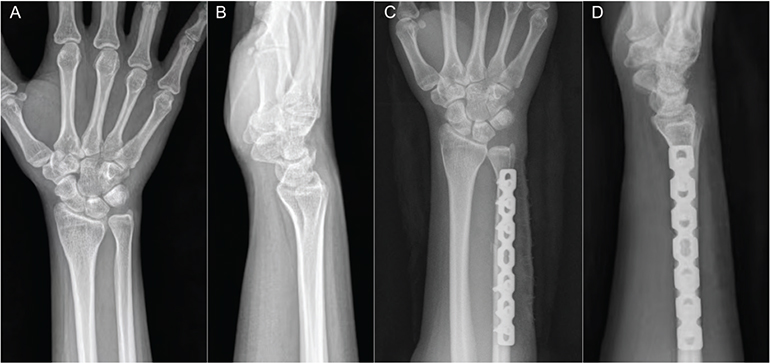

With the patient supine and a tourniquet applied to the upper arm, a longitudinal incision was made along the ulnar aspect of the distal forearm, starting at the ulnar neck. The dorsal ulna was exposed subperiosteally. A seven-hole dynamic compression plate (DCP) was temporarily positioned, with its distal end spanning from the ulnar neck to the sigmoid notch. The distal-most screw was inserted to establish plate position. An osteotomy site was marked between the third and fourth holes based on the preoperative ulnar variance. After removing the plate, osteotomy ends were marked with cautery to guide reduction. An oblique osteotomy was performed using a sagittal saw, and the resected segment was removed. The ulna was reduced along the marked axis, avoiding rotational malalignment. The DCP plate was reattached, and remaining screws were placed under dynamic compression to achieve stable fixation. Fluoroscopic imaging confirmed correction of ulnar variance and alignment (Figure 1). The incision was closed in layers (Figure 2).

Figure 2. A patient with ulnar impaction syndrome treated with oblique ulnar shortening osteotomy. (A) Preoperative posteroanterior radiograph of the right wrist. (B) Preoperative lateral radiograph of the right wrist. (C) Postoperative posteroanterior radiograph of the right wrist. (D) Postoperative lateral radiograph of the right wrist.